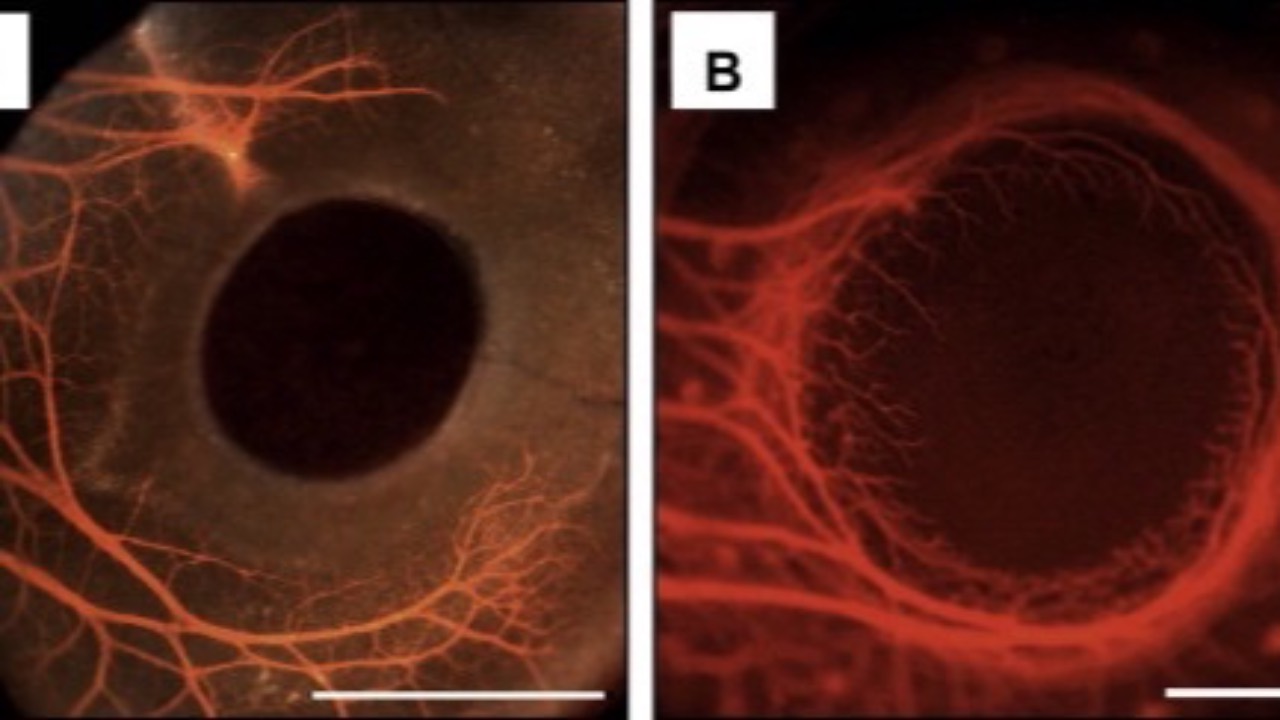

Sleep Apnea & AMD

Would you or would you not expect a link?...

A recent national cohort study found a relationship between obstructive sleep apnea (OSA) and age-related macular degeneration (AMD). The research focused on prevalence rates and risk factors, revealing a significant correlation between these two condi...